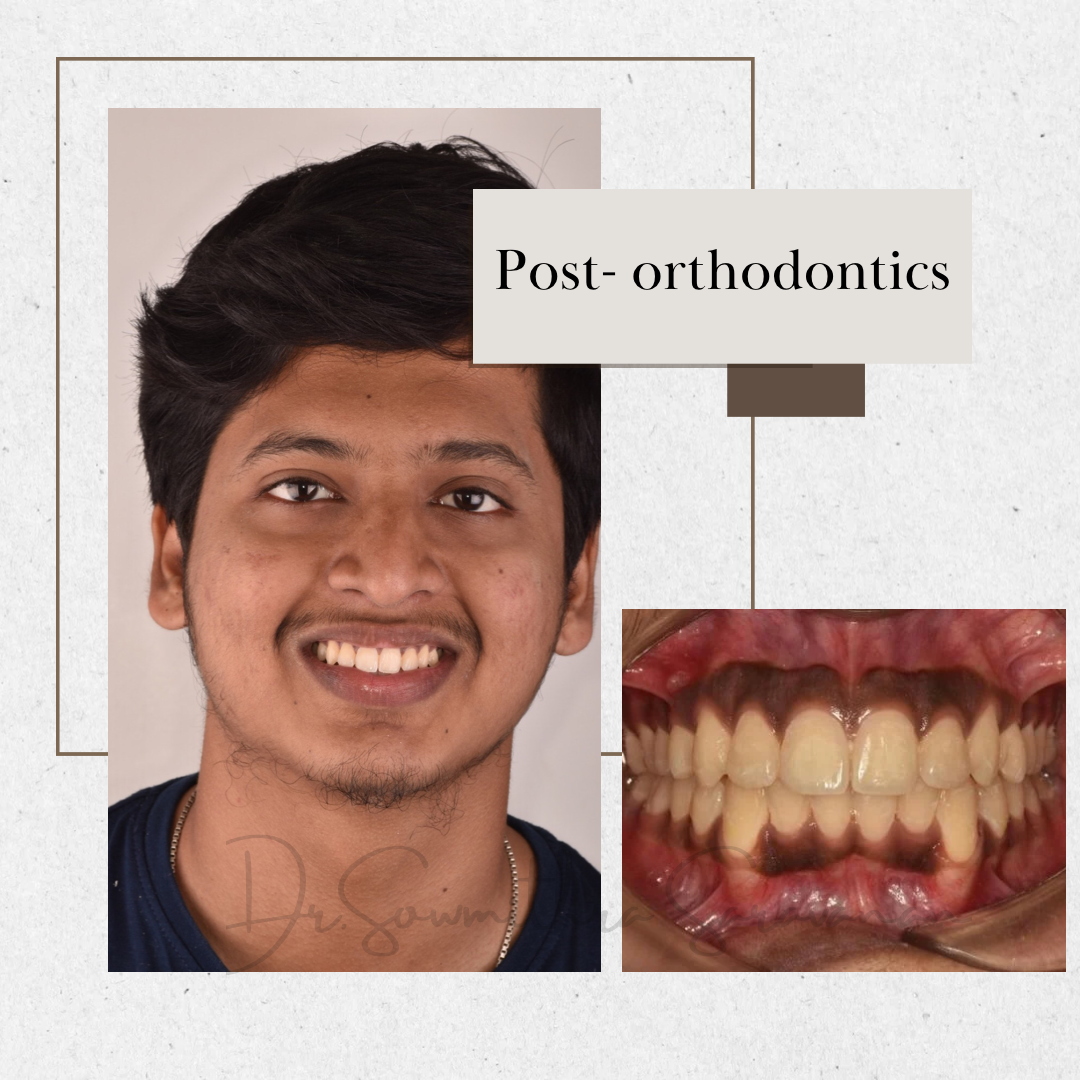

BRINGING OUT CONFIDENT SMILES- AN ORTHODONTIC SMILE REVEAL

BRINGING OUT CONFIDENT SMILES- AN ORTHODONTIC SMILE REVEAL